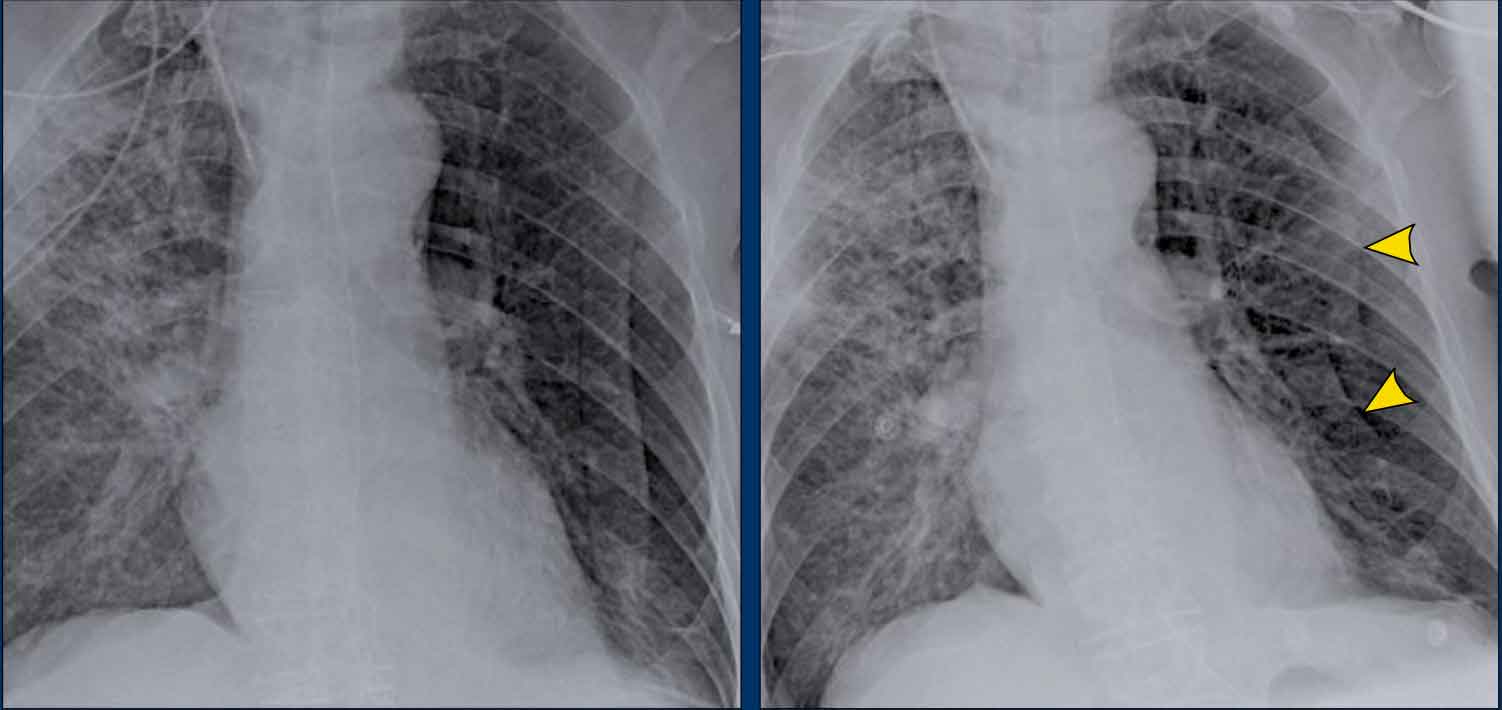

Case Example: Subtle Signs of Congestive Heart Failure

Begin by reviewing these current chest radiographs.

Based solely on these images, one might suspect congestive heart failure (CHF), though the findings are subtle.

Now review the previous study…

Scrolling between the current and prior films significantly increases diagnostic confidence in your diagnosis of congestive heart failure.

Key comparative findings include:

- Cardiac size: Slightly increased compared to the previous study; however, cardiomegaly was already present.

- Pulmonary vasculature: Mild vascular engorgement suggesting elevated pulmonary venous pressure.

- Interstitial markings: Subtle signs of interstitial edema .

- Pleural effusions: Bilateral small effusions, with subtle changes in the inferoposterior borders of the lower lobes, suggesting fluid accumulation.